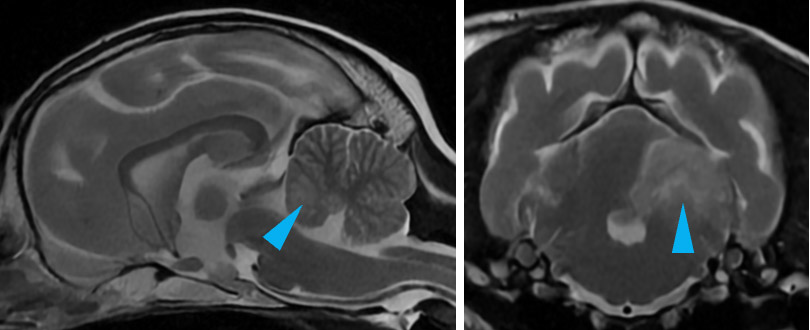

水頭症は脳室の異常な拡張を伴う疾患であり、チワワやポメラニアン、ヨークシャーテリア等の犬種では遺伝的に発生することがあります。臨床症状と脳室の拡張程度は必ずしも一致しませんが、症例によっては、性格の変化や視力の低下、しつけが困難であるなど意識・認知の低下がみられることもあります。

T2強調画像(左:正中矢状断像、右:横断像)